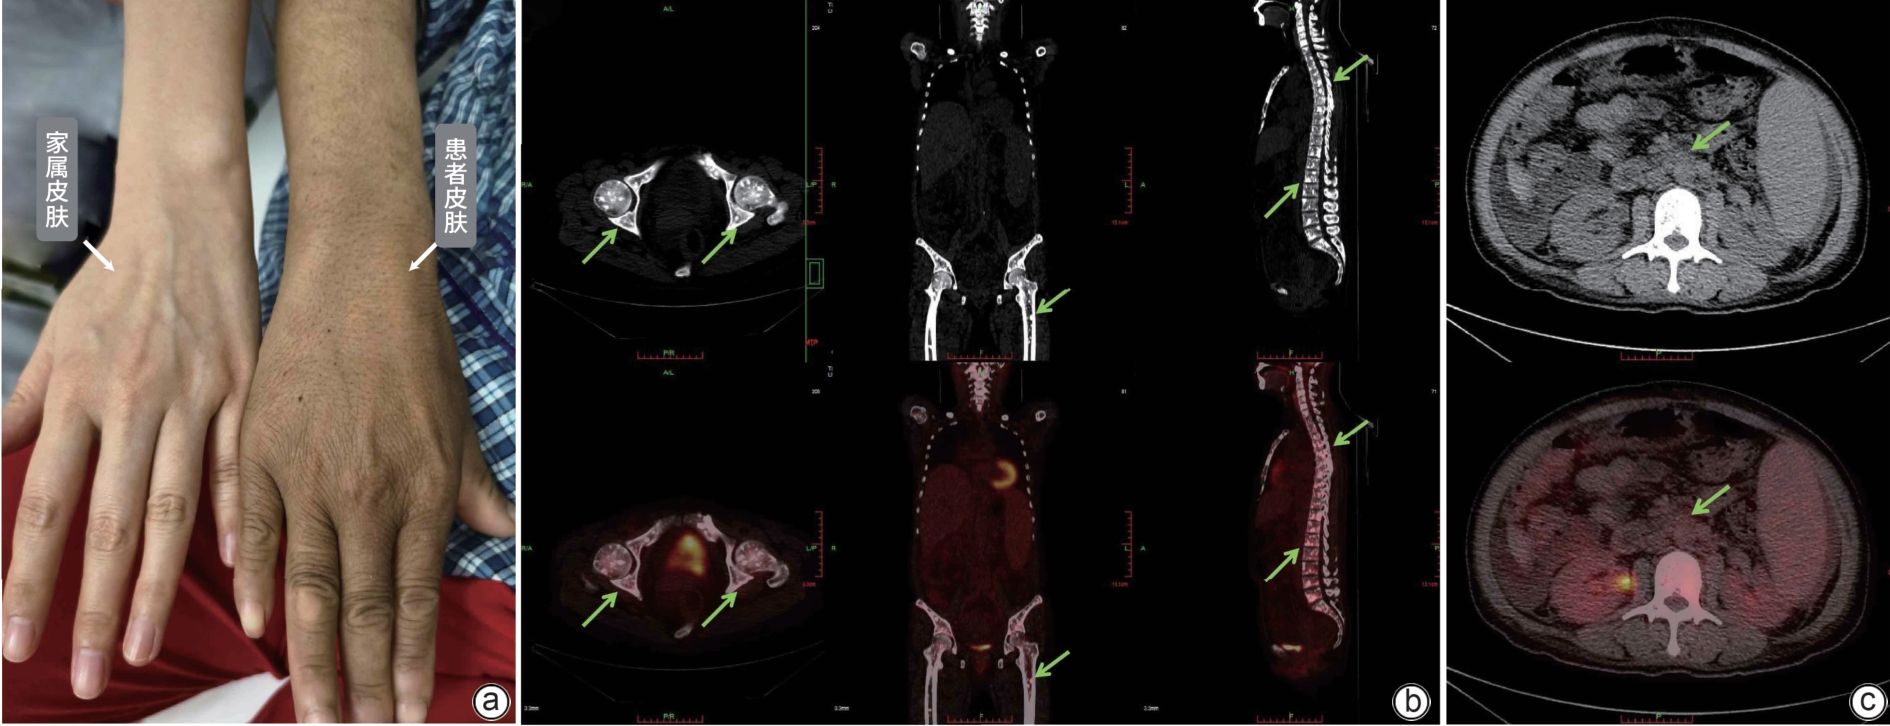

• POEMS syndrome is a rare condition associated with plasma cell disorders, and it often involves multiple systems and has diverse clinical manifestations. This article reports two cases of POEMS syndrome with hepatosplenomegaly as the initial manifestation. During the course of the disease, the patients presented with lower limb weakness, hepatosplenomegaly, lymph node enlargement, ascites, hypothyroidism, positive M protein, and skin hyperpigmentation, and 18F-FDG PET-CT imaging revealed bone lesions mainly characterized by osteolytic changes and plasma cell tumors. There was an increase in the serum level of vascular endothelial growth factor. The patients were finally diagnosed with POEMS syndrome, and the symptoms were relieved after immunomodulatory treatment.